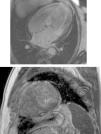

Cardiac magnetic resonance (CMR) showed marked concentric left ventricular (LV) hypertrophy, mild right ventricular (RV) hypertrophy and normal ejection fraction. There was biatrial enlargement, thickening of the interatrial septum and mild pericardial effusion (Figure 3). Short-tau inversion-recovery (STIR) sequences showed no myocardial edema or inflammation. In late gadolinium enhancement study, there was difficulty in setting the optimal inversion time to correctly null the myocardium, with a relatively dark blood pool and diffuse subendocardial enhancement of the interatrial septum and the LV and RV walls (Figure 4). The diffuse subendocardial late gadolinium enhancement, coupled with abnormal myocardial and blood-pool contrast kinetics, was most consistent with cardiac amyloidosis. The fact that the optimal inversion time that would null the normal myocardium could not be found is an indirect sign suggesting amyloidosis, because if abnormal fibrils are widespread in the intercellular space, the gadolinium may not be taken up by healthy myocardium.3

Cardiac magnetic resonance, 4-chamber view, depicting the late phase after gadolinium injection, with widespread subendocardial hyperenhancement of the left ventricle, not matching any coronary artery territory, but also involving the right ventricle, both atria and the interatrial septum.